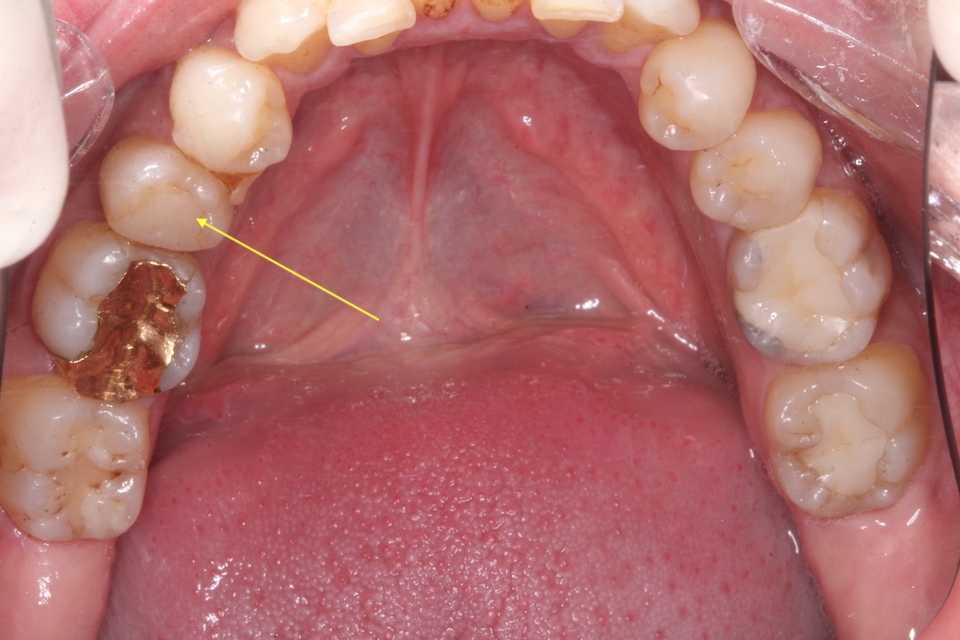

30代男性、右下5、Per

2年半ぶりにいらっしゃったので、口腔内規格写真での今日の画像です。

神経を取っているのでクラックは入りやすい。いずれ補強冠が必要になるだろう。

骨植は非常に良く問題なく生着・機能している。

歯列固定は1箇所を除いて脱離していたが、その1箇所も除去した。